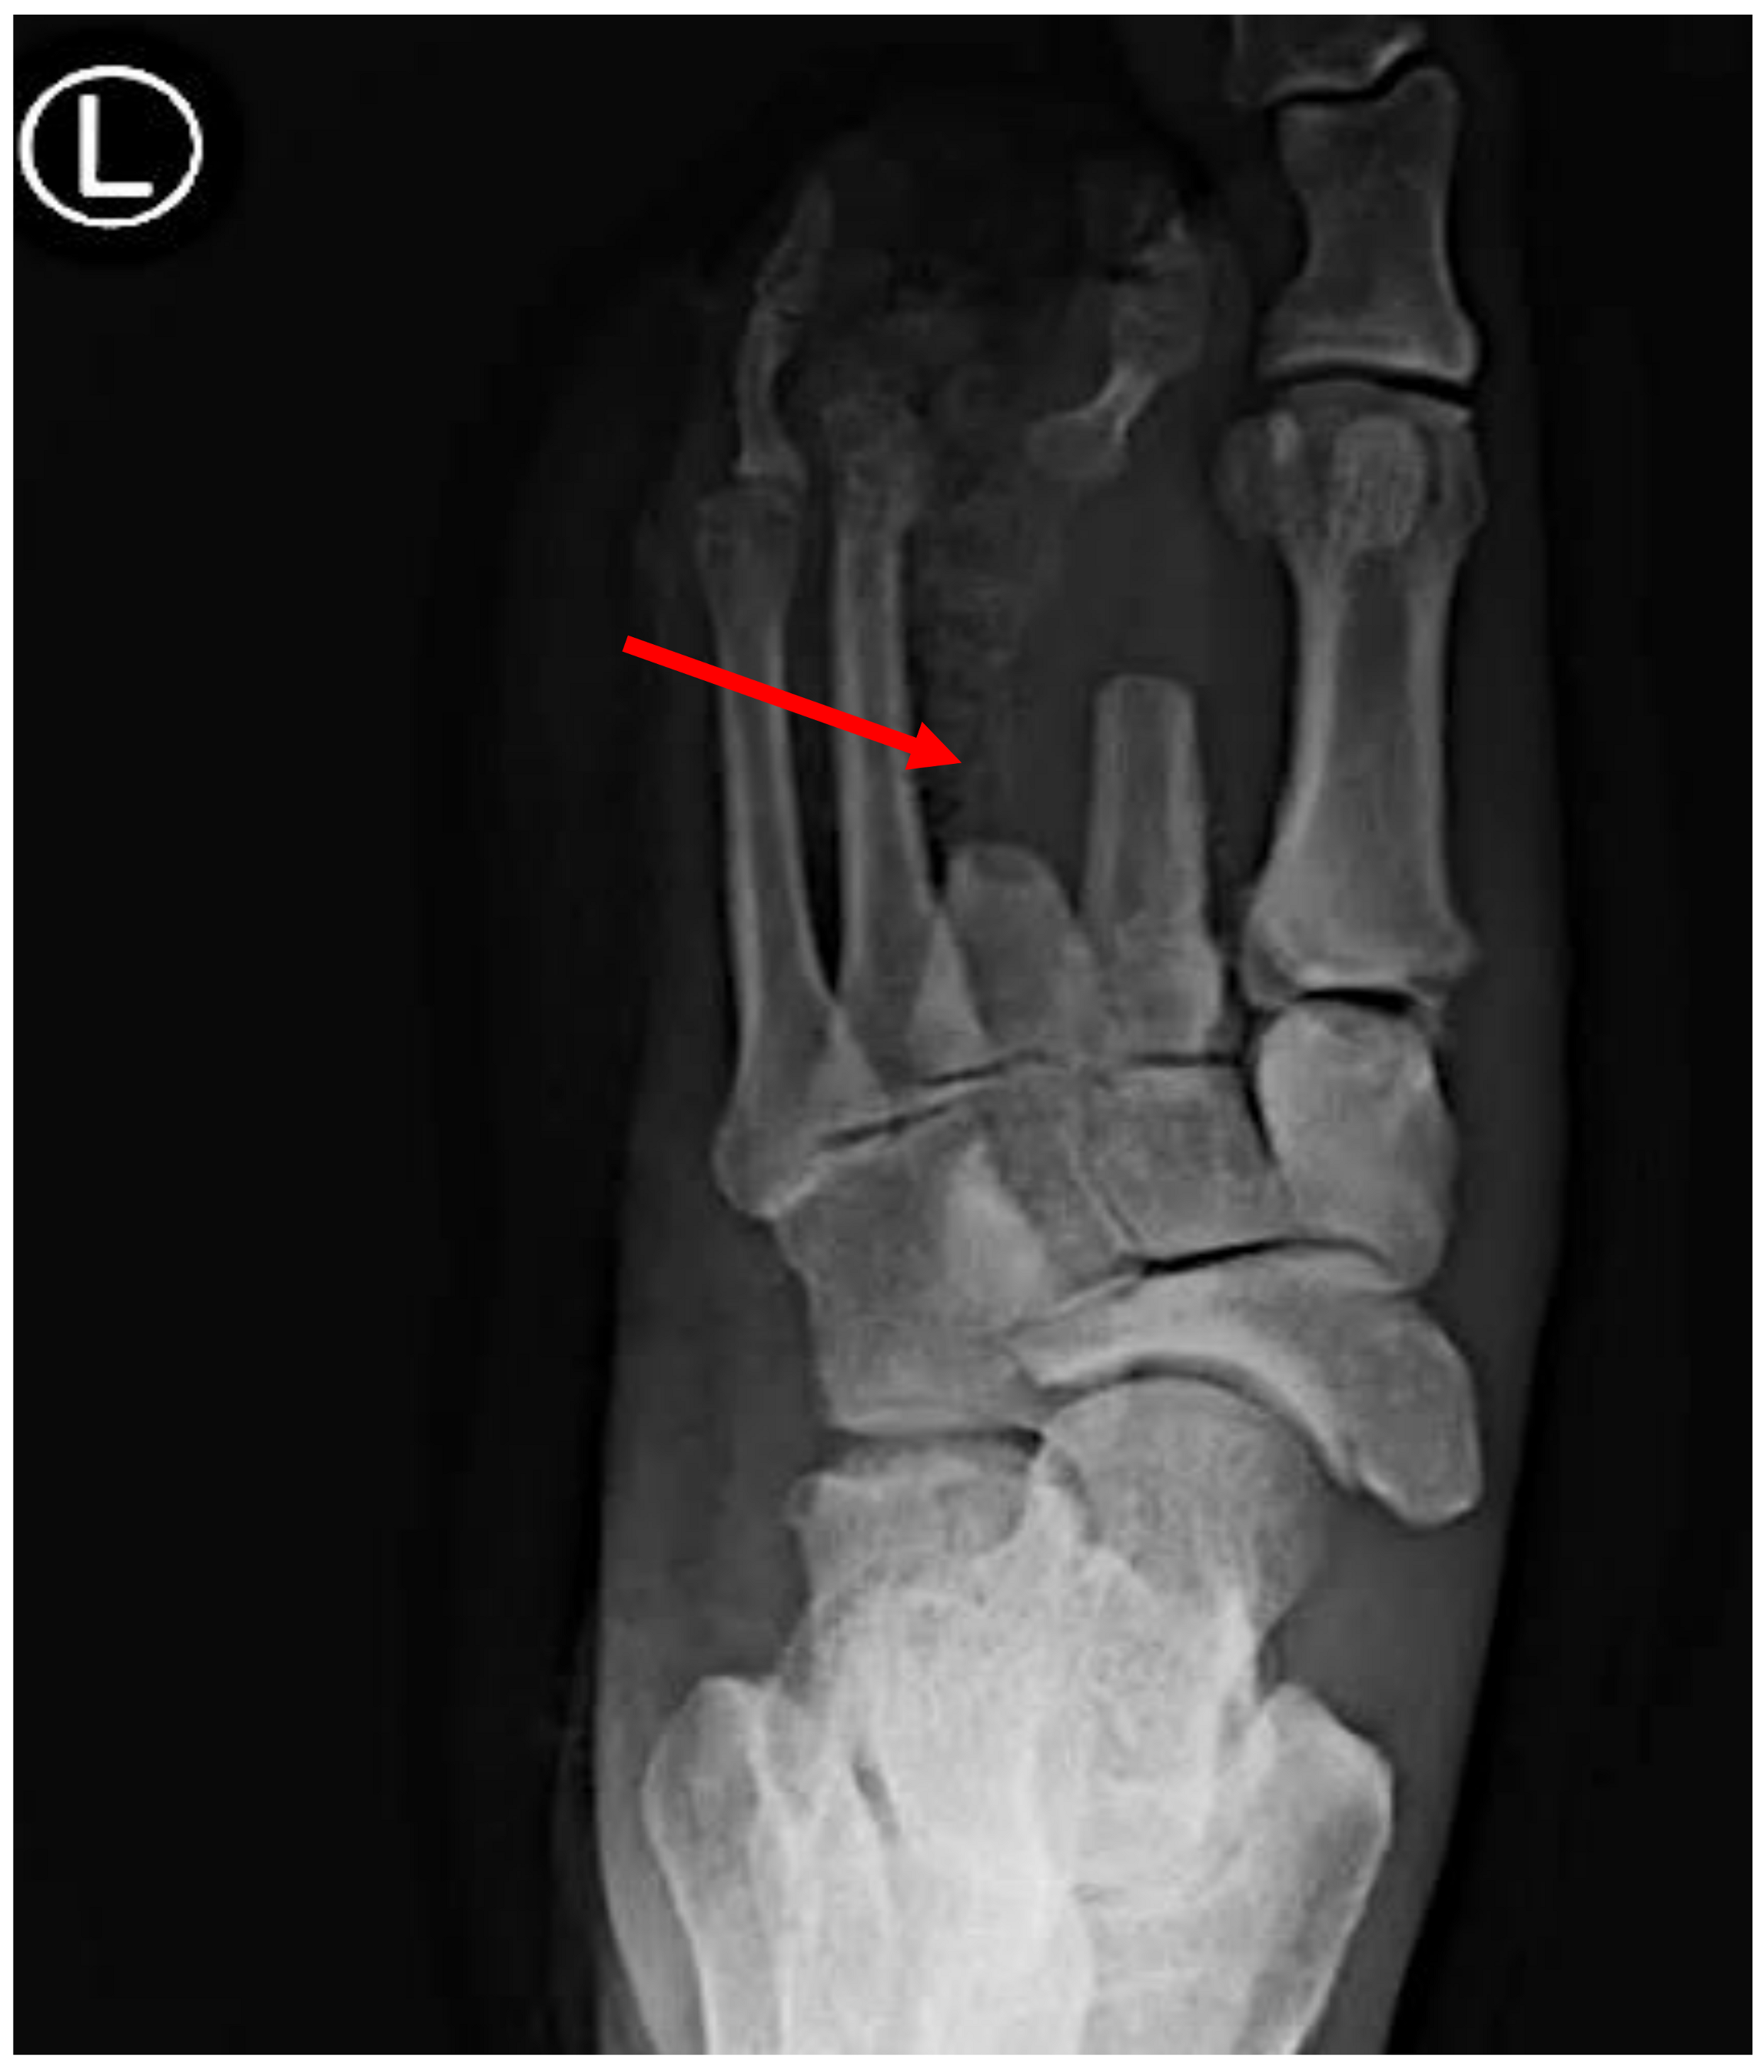

Spontaneous GG patients typically exhibit pronounced systemic symptoms of sepsis compared to traumatic cases [1,103]. The rapid onset of localized swelling, discoloration, and tenderness at the site of infection are common. Similar to traumatic GG, palpable crepitus may be present due to gas production within the affected tissue [101,102,103]. The dissemination of GG to the bone, resulting in osteomyelitis, is a possibility in non-traumatic cases, as evidenced by the presence of air-filled bullae, as observed in a foot presentation [1,2]. In rare instances, initial presentations may include confusion and other indicators of an altered mental state [2].

For example, one of our patients, a 40-year-old African American male, presented to the emergency department (ED) with fever and palpitations and was diagnosed with sepsis. Management in the ED included antibiotics and fluid resuscitation. The vital signs showed hypotension (100/61 mmHg), a temperature of 38.6 °C, a respiratory rate of 21 breaths per minute, and a pulse rate of 101 beats per minute. The physical examination revealed a toxic appearance, a 3 × 5 cm ulcer on the left plantar area with discharge, skin desquamation, and dark bullae on the posterior surface, with audible crepitus upon superficial examination. The peripheral pulses were preserved, and the remainder of the physical exam, including the neurological assessment, except for a sensation impairment in the affected area, was unremarkable. Four days prior, the patient had presented with left foot pain aggravated by movement, accompanied by shortness of breath and fatigue. Initial investigations showed a positive blood culture for CP, leukocytosis with neutrophil predominance on complete blood count, and X-ray evidence of gas within the left foot tissue. Additionally, elevated blood urea nitrogen, creatinine, and lactic acid levels were noted, while the other blood and urine laboratory results were within normal limits.

Imaging Studies: Imaging techniques like X-rays, ultrasound, or computed tomography (CT) scans may be used to assess the extent of tissue involvement, gas accumulation, and any associated complications, such as gas in the soft tissue or the involvement of deeper structures (Figure 3). Furthermore, magnetic resonance imaging (MRI) is essential in the management of GG by accurately delineating soft tissue involvement and detecting muscle edema, necrosis, and gas formation early on [1]. It plays a crucial role in differentiating GG from other infections, guiding surgical planning, and assessing the treatment response through the detailed evaluation of the extent and severity of muscle damage. MRI also facilitates targeted biopsy or drainage placement when needed, making it invaluable in both the diagnosis and therapeutic monitoring of this severe soft tissue infection.

Gas Detection: GG is typified by the production of gas within the affected tissue. Radiographic imaging techniques such as plain X-rays may unveil the presence of gas pockets, while ultrasound or CT scans can directly visualize the gas within the tissue, aiding in diagnosis and treatment planning [1,2].